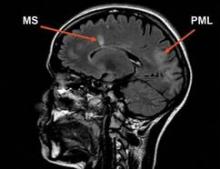

PML is an opportunistic brain infection caused by the JC virus. Previous estimates had put the incidence at about 1 case per 1,000. In April 2011, the Food and Drug Administration reported that 102 cases of PML had been reported among 82,732 patients treated with natalizumab worldwide.

The incidence of PML rises to as much as 11.1 per 1,000 in multiple sclerosis patients who are positive for anti-JC virus antibodies, who have taken immunosuppressants before starting natalizumab, and who have taken the drug for 25-48 months.